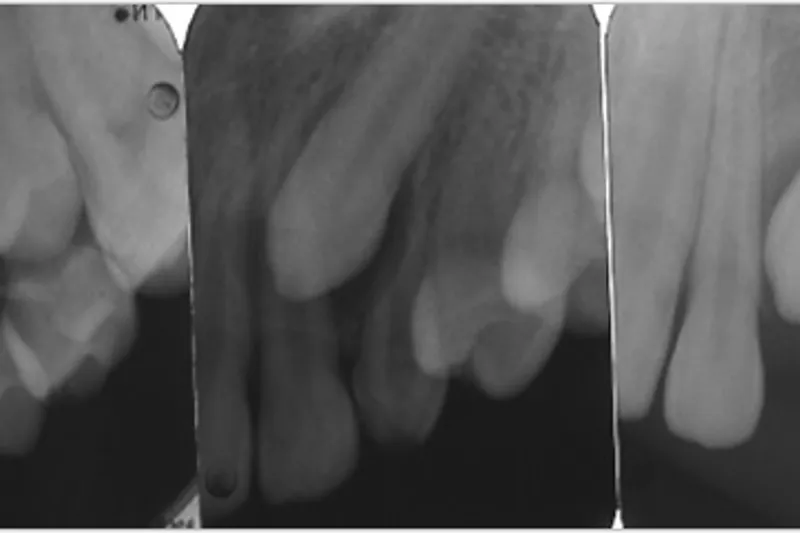

Egne patienteksempler viser spontane effekter af rettidig ekstraktion af mælketænder ved hjørnetandsektopi eller agenesi af præmolarer.

Patienteksempler viser ortodontisk lukning ved agenesi af den maksillære laterale incisiv, ved agenesi af den mandibulære 2. præmolar eller ved agenesi af flere præmolarer i samme kvadrant.